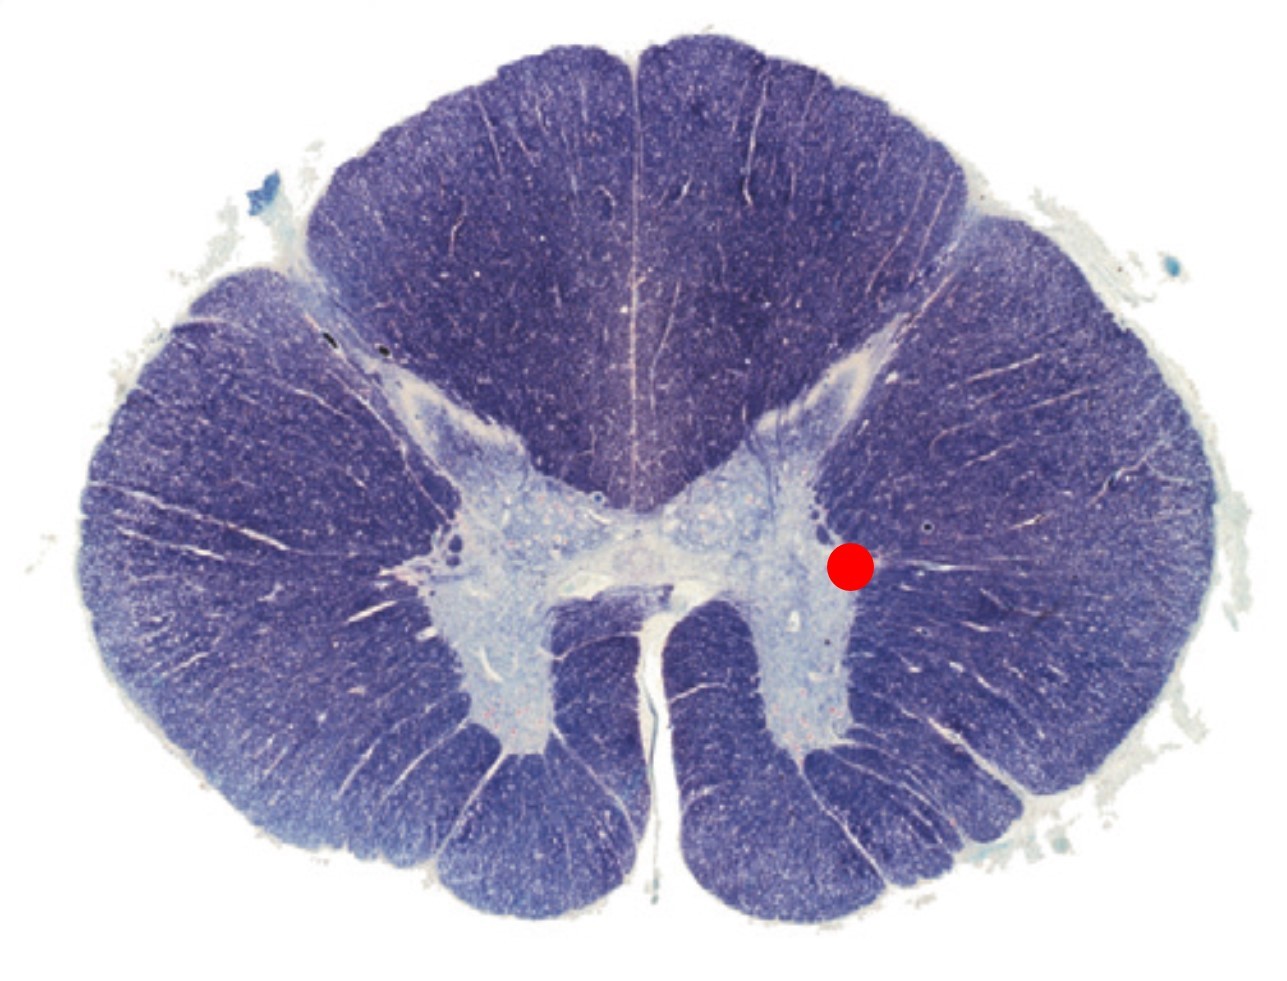

The cross section corresponds to which level of the spinal cord:

A

Thoracic